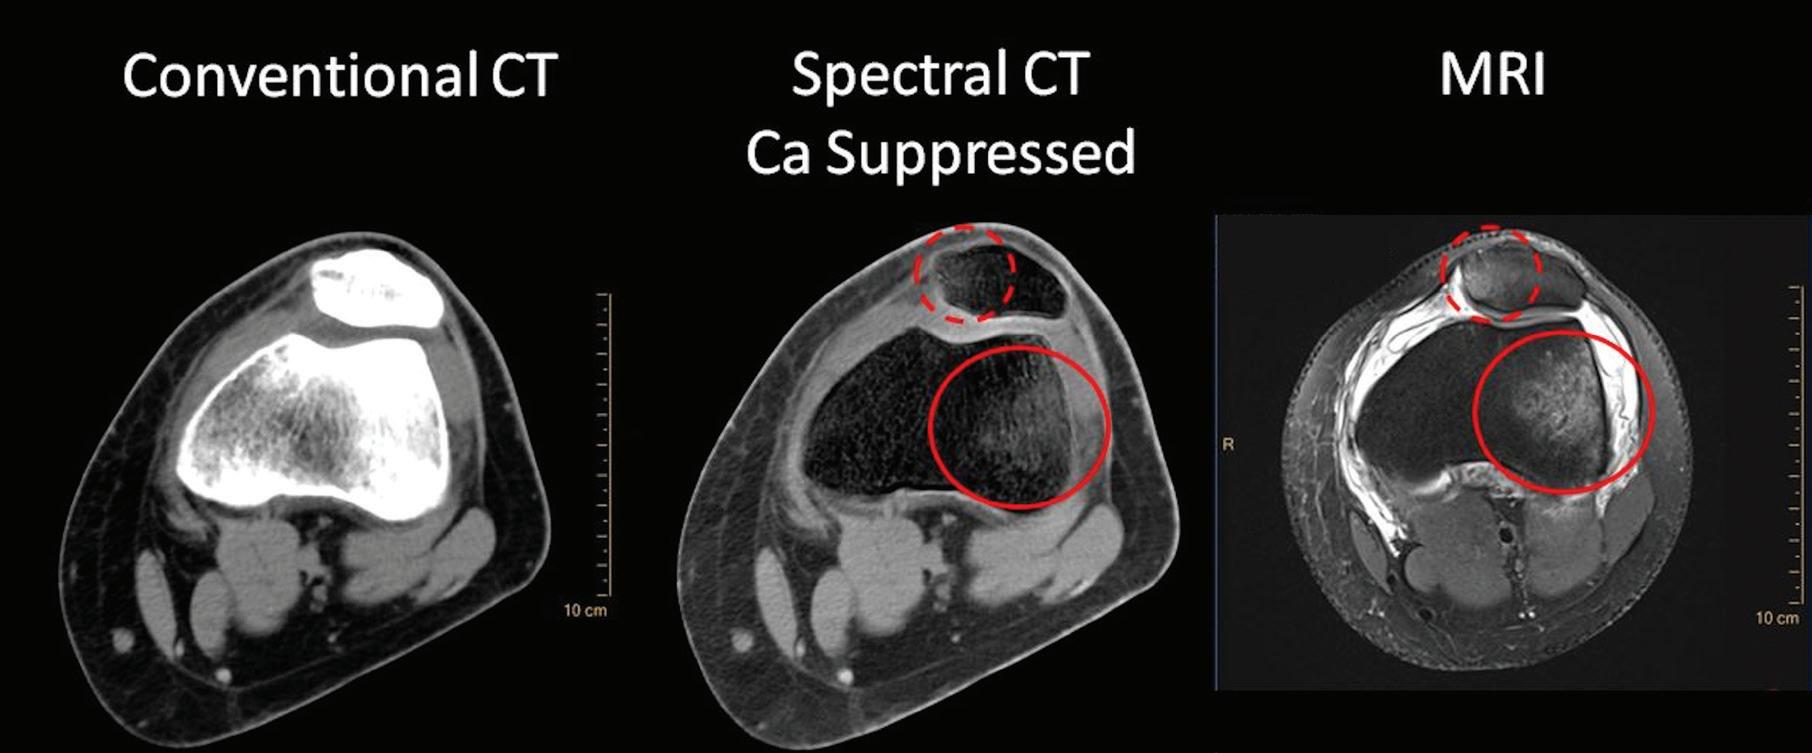

Calcium Suppression (CaSupp) [HU]

Are images that display the attenuation without the attenuation contribution of calciumbased materials.13 Same as the iodine suppression in VNC, but for various calcium-based material. A higher calcium suppressed Index (CSI) corresponds to a higher calcium composition weight (Figure 7).

As Alvarez and Macovski wrote, the optimal material base must be selected phenomenologically taking into account the energy range and the materials the X-ray beam is expected to transverse. If bone and water are chosen as the base materials for the decomposition, the information from the low and high attenuation data can be used to calculate the bone coefficients of the X-ray attenuation. These coefficients can then be used to create a bone image which allows the assessment of bony structures and calcifications. Alternatively, the water coefficients can be calculated to generate a soft tissue image where the bony structures are suppressed and which improves the visualization of structures previously hidden by bony anatomy. Any material pairs can be created from any other pairs as a linear transformation post-decomposition: a change of base. Other pairs of base materials with clinical relevance are iodine and calcium, iodine and water, or calcium and water. In cardiovascular imaging, the iodine images from an iodine-calcium pair can be of primary importance because they can help to better assess the iodinated lumen of the arteries which could be otherwise hidden by the presence of large calcified plaques. The water images from an iodine-water pair are ones in which all of the iodine is removed. These virtual non-contrast images (VNC) synthesize a pre-contrast scan.11,12 The water images from a calcium-water pair are ones in which all of the calcium is removed. These calcium suppressed images (CaSupp) can be used to improve the visualization of the bone marrow edema which is partially hidden by the presence of the bony structures in the conventional CT images.13

In practice, a single CT scan is performed (e.g., 120 kVp or 140 kVp), and the first layer (upper) encountered by the X-ray photons absorbs most of the low-energy photons, while the bottom detector layer absorbs the remaining higher energy photons (Figure 1). In contrast to other approaches of dual-energy CT, there is no need to redundantly expose materials with both low and high kVp. Furthermore, since the spectral energy separation is intrinsic to the detection system, rather than sequentially generated at the X-ray source, this approach eliminates the time lag of sequential techniques, making it ideal for imaging moving organs, as in cardiac CT. In other words, the dual-layer technique is fully registered both spatially and temporally, and it has no spatial shift or dead time such as in dual kVp or dual tube techniques. The low- and high-energy projection data are perfectly aligned, enabling projection-based spectral decomposition, and providing the opportunity to properly account for beam hardening effects without the need for spatial or temporal interpolations.6,7